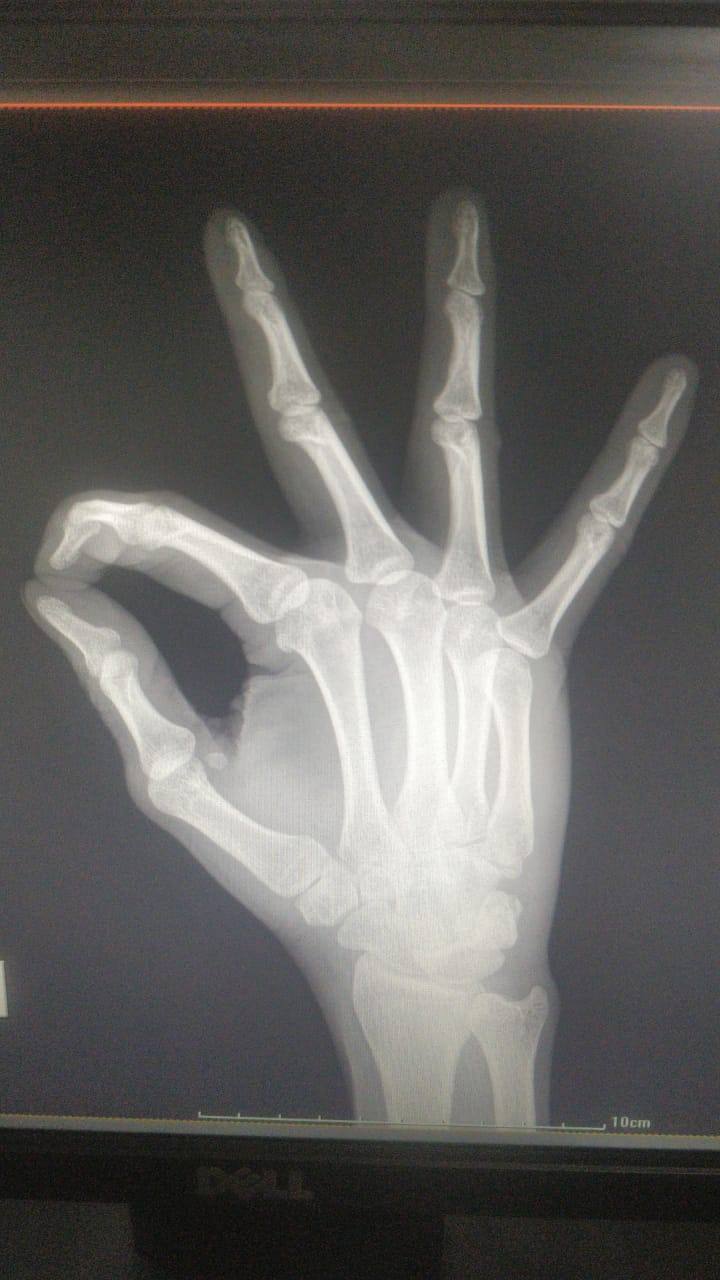

5th metacarpal hair line fracture Required surgery or not? Because doctor suggest me for surgery please reply as soon as possible sir.

5th metacarpal hair line fracture Required surgery or not ??